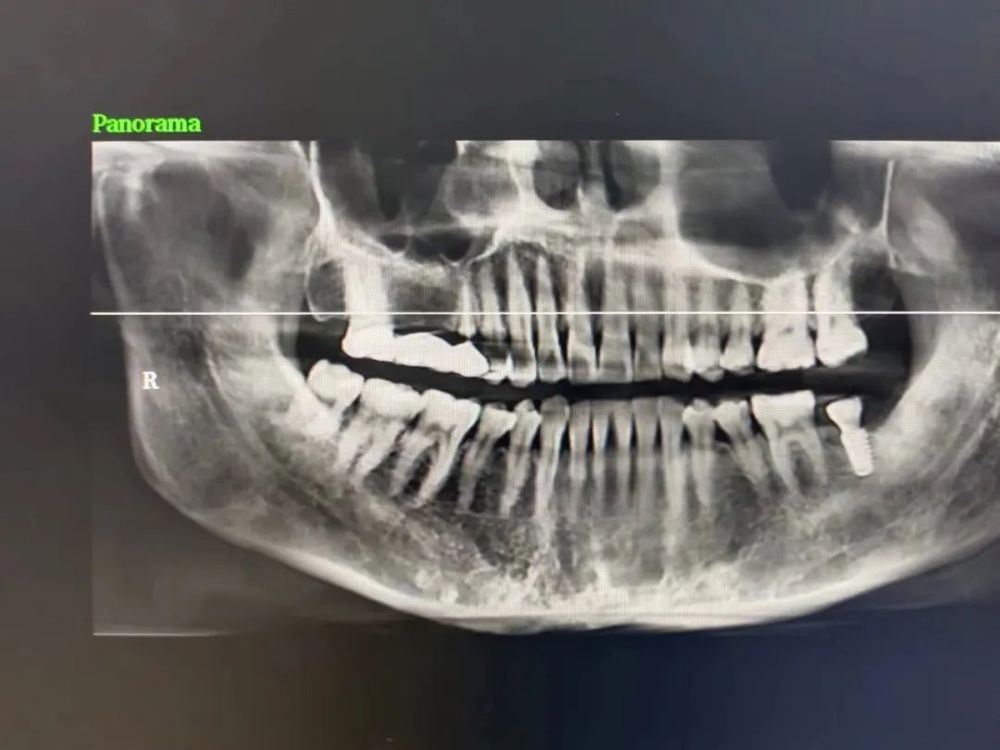

三、種植牙技術

目(mù)前,社會上很多(duō)人被牙齒缺失所(suǒ)困擾,牙齒缺失不但影響人的咀嚼和(hé)語言功能,對於人的(de)麵(miàn)部(bù)美觀也是一種影響,甚至有些人因(yīn)缺失牙齒而(ér)不願意張口說話,種植牙被譽為(wéi)人類“第(dì)三(sān)副牙齒”,因其舒適(shì)、美觀(guān)、功能(néng)好而被缺牙患者追捧。經衛生(shēng)健康委批準,我院於2023年(nián)3月18日正式(shì)開展種植(zhí)牙技術,開(kāi)展當天門診手術7例共計14顆植體,術(shù)後1天回訪患者表示無紅腫、無疼痛症狀(zhuàng),術後(hòu)7天回訪(fǎng)一切良好無異常,術後10天拆線創口愈合良好,自開展口(kǒu)腔種植手術以來,有許多患者紛紛到科裏(lǐ)進行相關谘詢和(hé)檢查,更是不斷有患(huàn)者預約意向種植,我院嚴格按照江(jiāng)西省醫療保障局、江西省衛生健康委員(yuán)會(huì)關於(yú)公布實施口腔種植類醫療服務價格有關事項的通知—贛醫保字《2023》3號文(wén)件執行操作,在手術診療中,嚴(yán)格操作流程,減少感染風險。我院(yuàn)口腔種植技術的成功和發展,不僅完善了傳(chuán)統牙齒修複(fù)技術的不(bú)足,而且在功能與(yǔ)美觀上給了(le)人們嶄新的體驗,我院致力於提供一站式口腔種植診療服務,必將為(wéi)本縣及周邊缺(quē)失牙患者找回美麗、自信的微笑。

案例(lì)一

種植前與種植後

案例二

種植前與種植(zhí)後